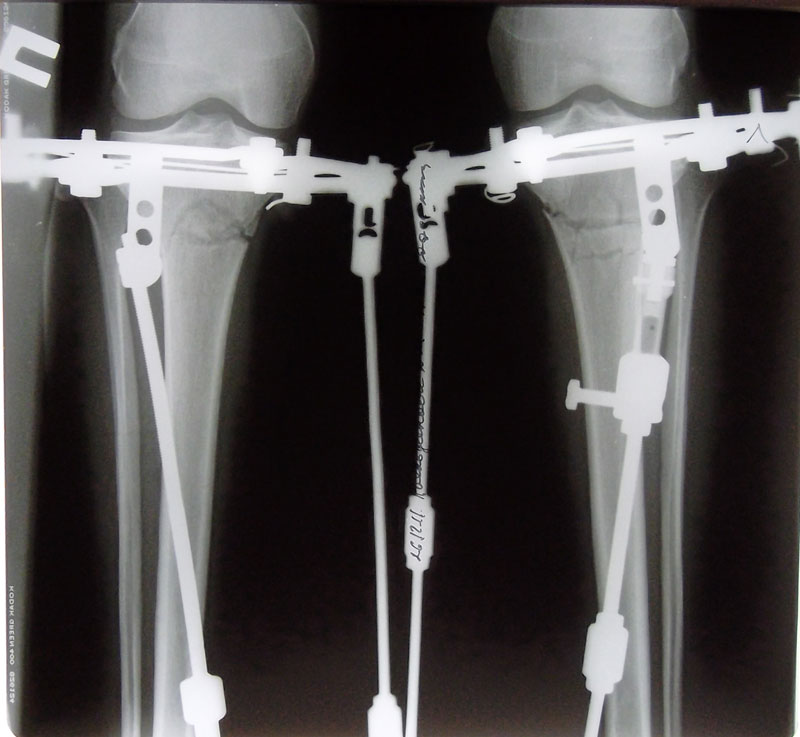

Здравствуйте, Николай Николаевич! Как и обещала, высылаю Вам снимки через 1 месяц с момента операции.

Здравствуйте, Румия! Рентгеновские снимки замечательные, всё идёт по плану.